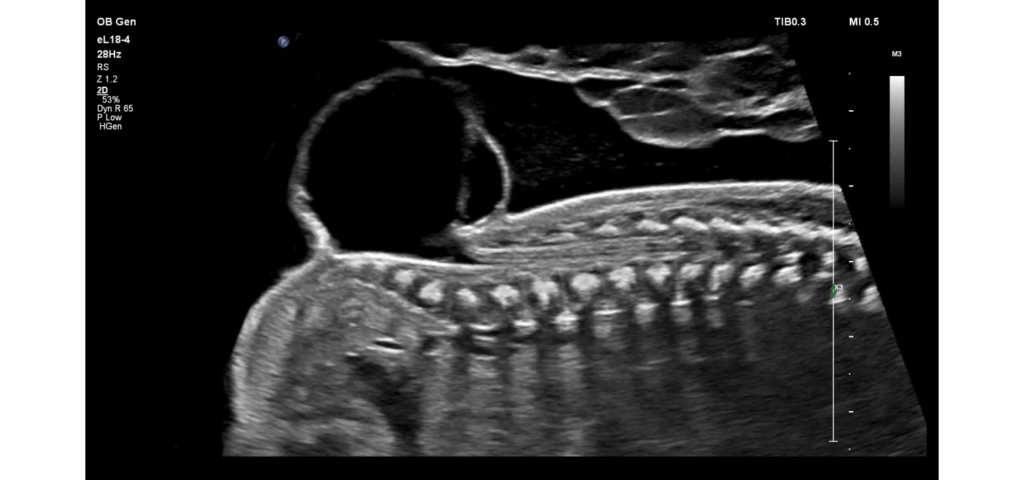

Philips EPIQ Elite ultrasound features an exceptional level of clinical performance, workflow, and advanced intelligence to meet the challenges of today’s most demanding practices. The EPIQ Elite platform brings ultimate solutions to ultrasound, with clinically tailored tools designed to elevate diagnostic confidence to new levels.